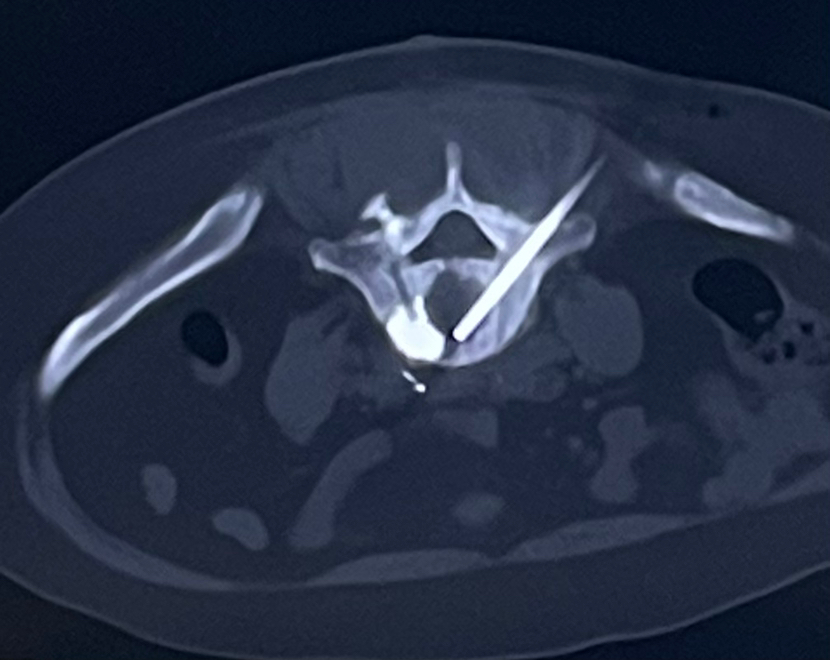

骨穿刺活检注意事项:1.穿刺活检前应尽量行增强CT或MRI扫描,避开坏死区域取材且尽可能在溶骨性区域取材,以满足常规病理及分子病理学诊断的要求;2.为了明确诊断,骨活检应在任何治疗前进行;通常情况下,穿刺活检不会引起病理性骨折事件的发生;骨转移病灶的活检应遵循肌肉骨骼系统肿瘤活检取材的原则组织。